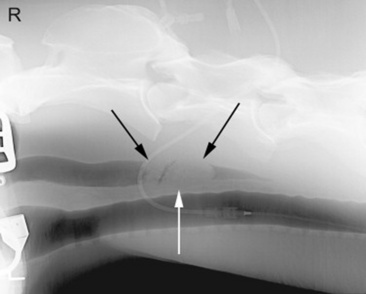

Survey radiography is generally helpful to evaluate the cervical esophagus for evidence of rupture as well as to evaluate the abdomen. Esophageal ruptures secondary to an obstruction or vigorous placement of a nasogastric tube result in a small volume of gas that tracks just dorsal to the trachea (Fig. 32-2). This can be confused with a tracheal laceration; however, with tracheal lacerations generally the gas accumulation will surround the trachea and the volume of gas within the subcutaneous tissues and the cranial mediastinum will be severe. In addition, esophageal obstructions, also called choke, can sometimes be identified on survey radiographs depending on the material that is causing the obstruction and the amount of air or contrast medium that is able to surround the structure (Fig. 32-3). Although the nature of the obstruction cannot be determined, the extent of the abnormality can sometimes be identified.

Fig. 32-2 Standing lateral radiograph of a 13-year-old Morgan gelding with an esophageal tear. Note the tubular region of small gas opacities caused by air trapped around the outer border of the esophagus (arrows). An esophageal perforation secondary to an ingested foreign body was confirmed with endoscopy.